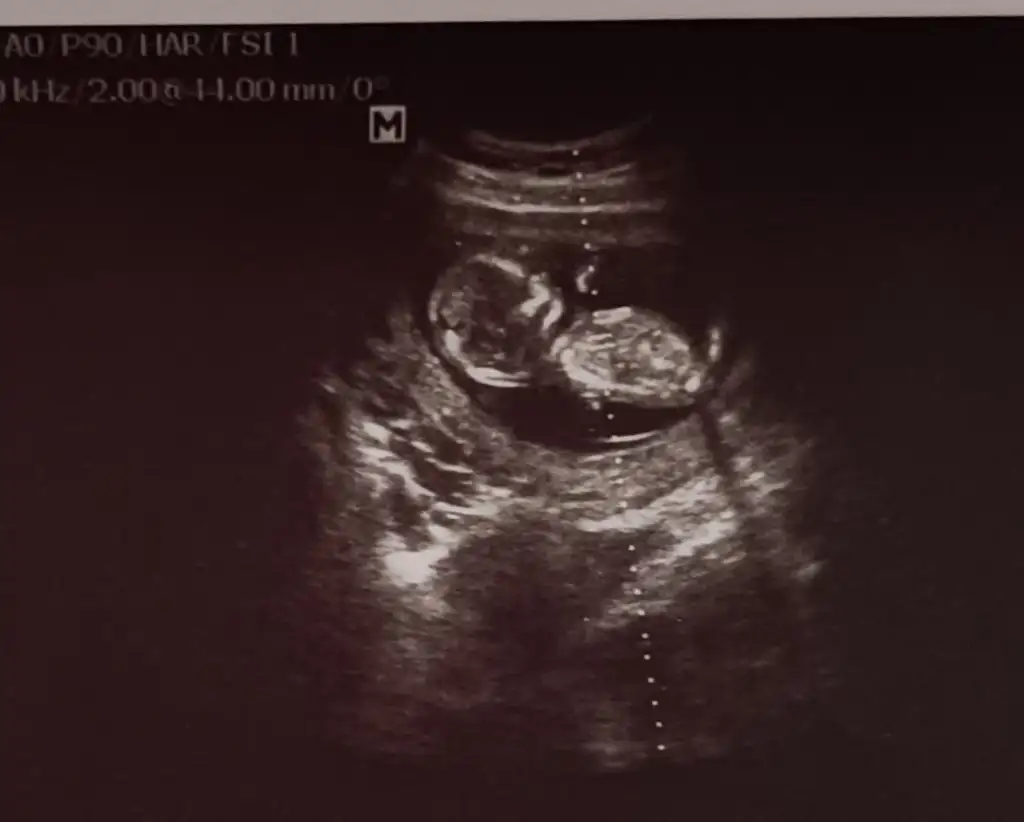

Merhaba arkadaşlar sat göre 12+2 usg göre 13+0

Dr baktı bebiş göstermedi cinsiyeti öğrenemedim. Merak ettim nub dan anlayan var mı